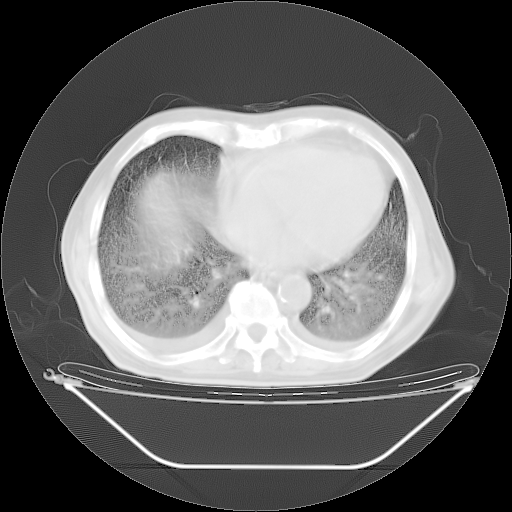

今天复查肺部CT,发现双肺广泛磨玻璃样改变。所以我把3月19日和5月9日相隔50天的肺部CT上传。请大家会诊。

2009年3月19日肺部CT片。

2009年3月19日肺部CT